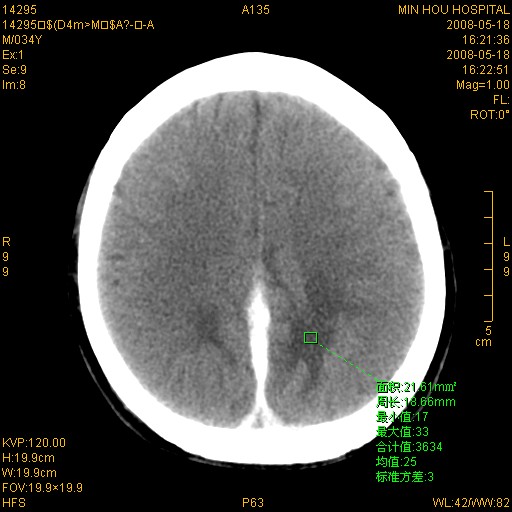

标题: CT13617:双顶叶白质水肿伴大脑镰小脑幕广泛钙化 [打印本页]

标题: CT13617:双顶叶白质水肿伴大脑镰小脑幕广泛钙化

多年前频发抽搐生活不能自理,行ct平扫,诊断为双顶叶占位。因贫未能进一步检查。

目前偶有抽搐,能从事油漆工作。原片未能获取。

双侧侧脑室后脚旁对称性低密度影,符合肾上腺白质营养不良(成人型)改变    小脑幕及大脑廉钙化  可考虑为生理性

支持:1、肾上腺白质营养不良.2、小脑幕、大脑镰广泛钙化。3、建议进一步检查。

硬脑膜钙化是主因,双侧顶叶白质密度减低是可能由于静脉路回流受阻所致。